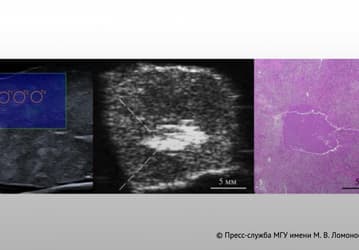

Новая форма иммунотерапии бьёт по раку точнее и с меньшими побочными эффектами

Лекарство научили «включаться» только в больных тканях